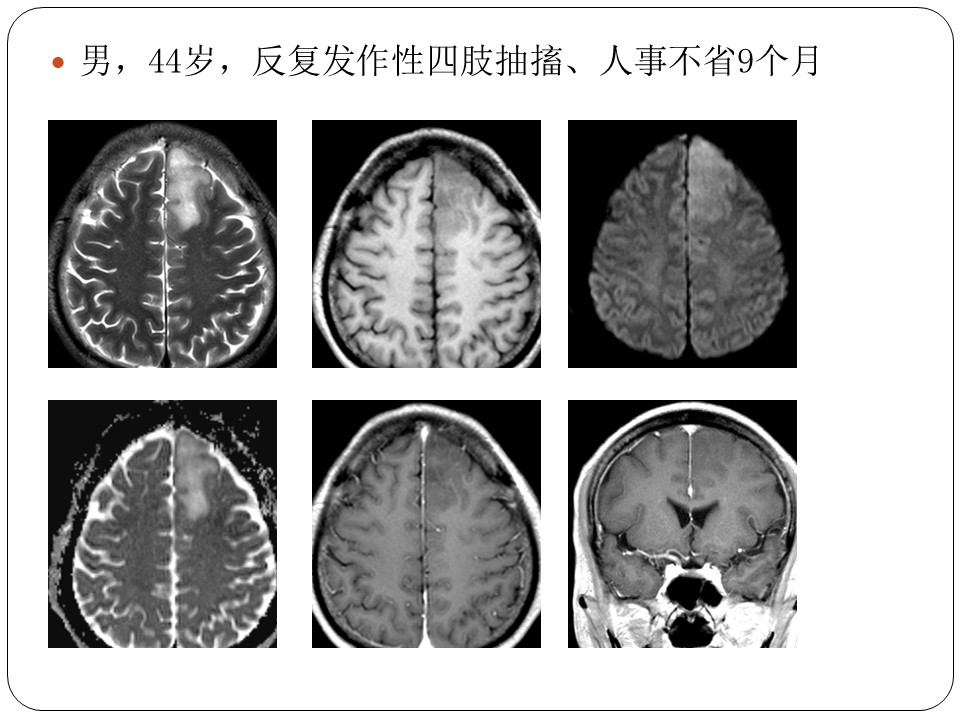

抽搐

抽搐意识丧失,头后仰,眼球上翻,四肢强直,持续10-20s尖叫、呼吸暂停、面唇发绀、瞳孔散大、尿便失禁发作后转入昏迷状态...